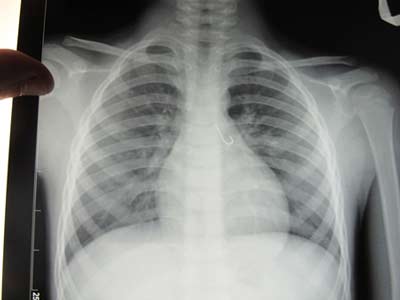

Bản chụp X-Quang thấy rõ lưỡi câu mắc trong phổi bệnh nhi

Bệnh nhi N.X.T 7 tuổi, là người dân tộc Cơ tu thường trú tại huyện Nam Trà My, tỉnh Quảng Nam. Trước đó, ngày 10/9, bệnh nhi nhập viện trong tình trạng ngột thở, ho sặc sụa. Qua nội soi cấp cứu, phát hiện 1 lưỡi câu còn nguyên móc, dài 1,5cm mắc ở phổi. Lưỡi câu cắm vào niêm mạc của phế quản. Các bác sĩ đã tiến hành phẫu thuật cấp cứu lấy lưỡi câu ra khỏi phổi bệnh nhi an toàn. Qua theo dõi điều trị, hiện sức khỏe bệnh nhi đã bình phục hoàn toàn.

Điều tra bệnh lý, người nhà bệnh nhi cho biết: trong lúc đi câu cá với các bạn, sợ các bạn giành mất lưỡi câu nên cháu ngậm giấu lưỡi câu trong miệng. Không may, cháu để lưỡi câu tuột luôn xuống họng. Khi cháu bị ngạt thở nguy cấp, người nhà đưa ra viện điều trị mới tá hỏa khi biết lưỡi câu mắc hẳn vào trong phổi. Các bác sĩ chuyên khoa nhận định, rất may cháu bé được cấp cứu kịp thời, không thì khó tránh khỏi nguy cơ thiệt mạng.